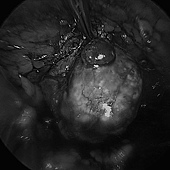

這兩種就比較建議做腎上腺切除手術,但腎上腺很深,傳統上要開一個相當大的傷口才能處理的到,現在因為腹腔鏡的發展,我們只需要打幾個小洞,將器械伸進去處理即可,恢復時間大幅縮短。

💁🏻♂️ 上面這位病人後來查出是腎上腺腫瘤所引發的「原發性高醛固酮症」,就是經由腹腔鏡腎上腺切除後,隔天的電解質立刻回復到正常了,而且目前也不再需要吃降血壓藥了!